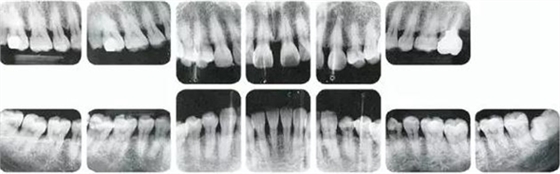

25歲女性。菌斑控制狀態(tài)不好。齦溝除磨牙處外全在3mm以下,X光照片上左上、右下、左下的第一磨牙上有垂直性骨吸收。這個(gè)病例是參考病例①10年前的狀態(tài),是典型的侵襲性牙周炎局部型。

牙周病的發(fā)展因部位不同而發(fā)展程度不同的。10點(diǎn)后的狀態(tài)參考病例①和參考病例②的磨牙處的狀態(tài)相比較,思考下沒(méi)接受治療病情發(fā)展的特別性吧。

在左下第一磨牙在25歲時(shí)近中處可以看到垂直性的骨吸收,但35歲時(shí)吸收停止,原本沒(méi)有見(jiàn)到的遠(yuǎn)中處骨吸收的,現(xiàn)在卻吸收得很嚴(yán)重。

在右下處,原本有大量骨吸收的第一磨牙處的吸收卻變緩慢,原本沒(méi)有吸收的第二前磨牙卻出現(xiàn)了吸收。出現(xiàn)吸收的左上第一磨牙的遠(yuǎn)中處,吸收得越來(lái)越多了。

把10年間的變化做成表格。牙周病的發(fā)展根據(jù)各個(gè)人會(huì)不同,即使通一個(gè)人,不同牙齒,不同牙面發(fā)展的狀態(tài)也不同。